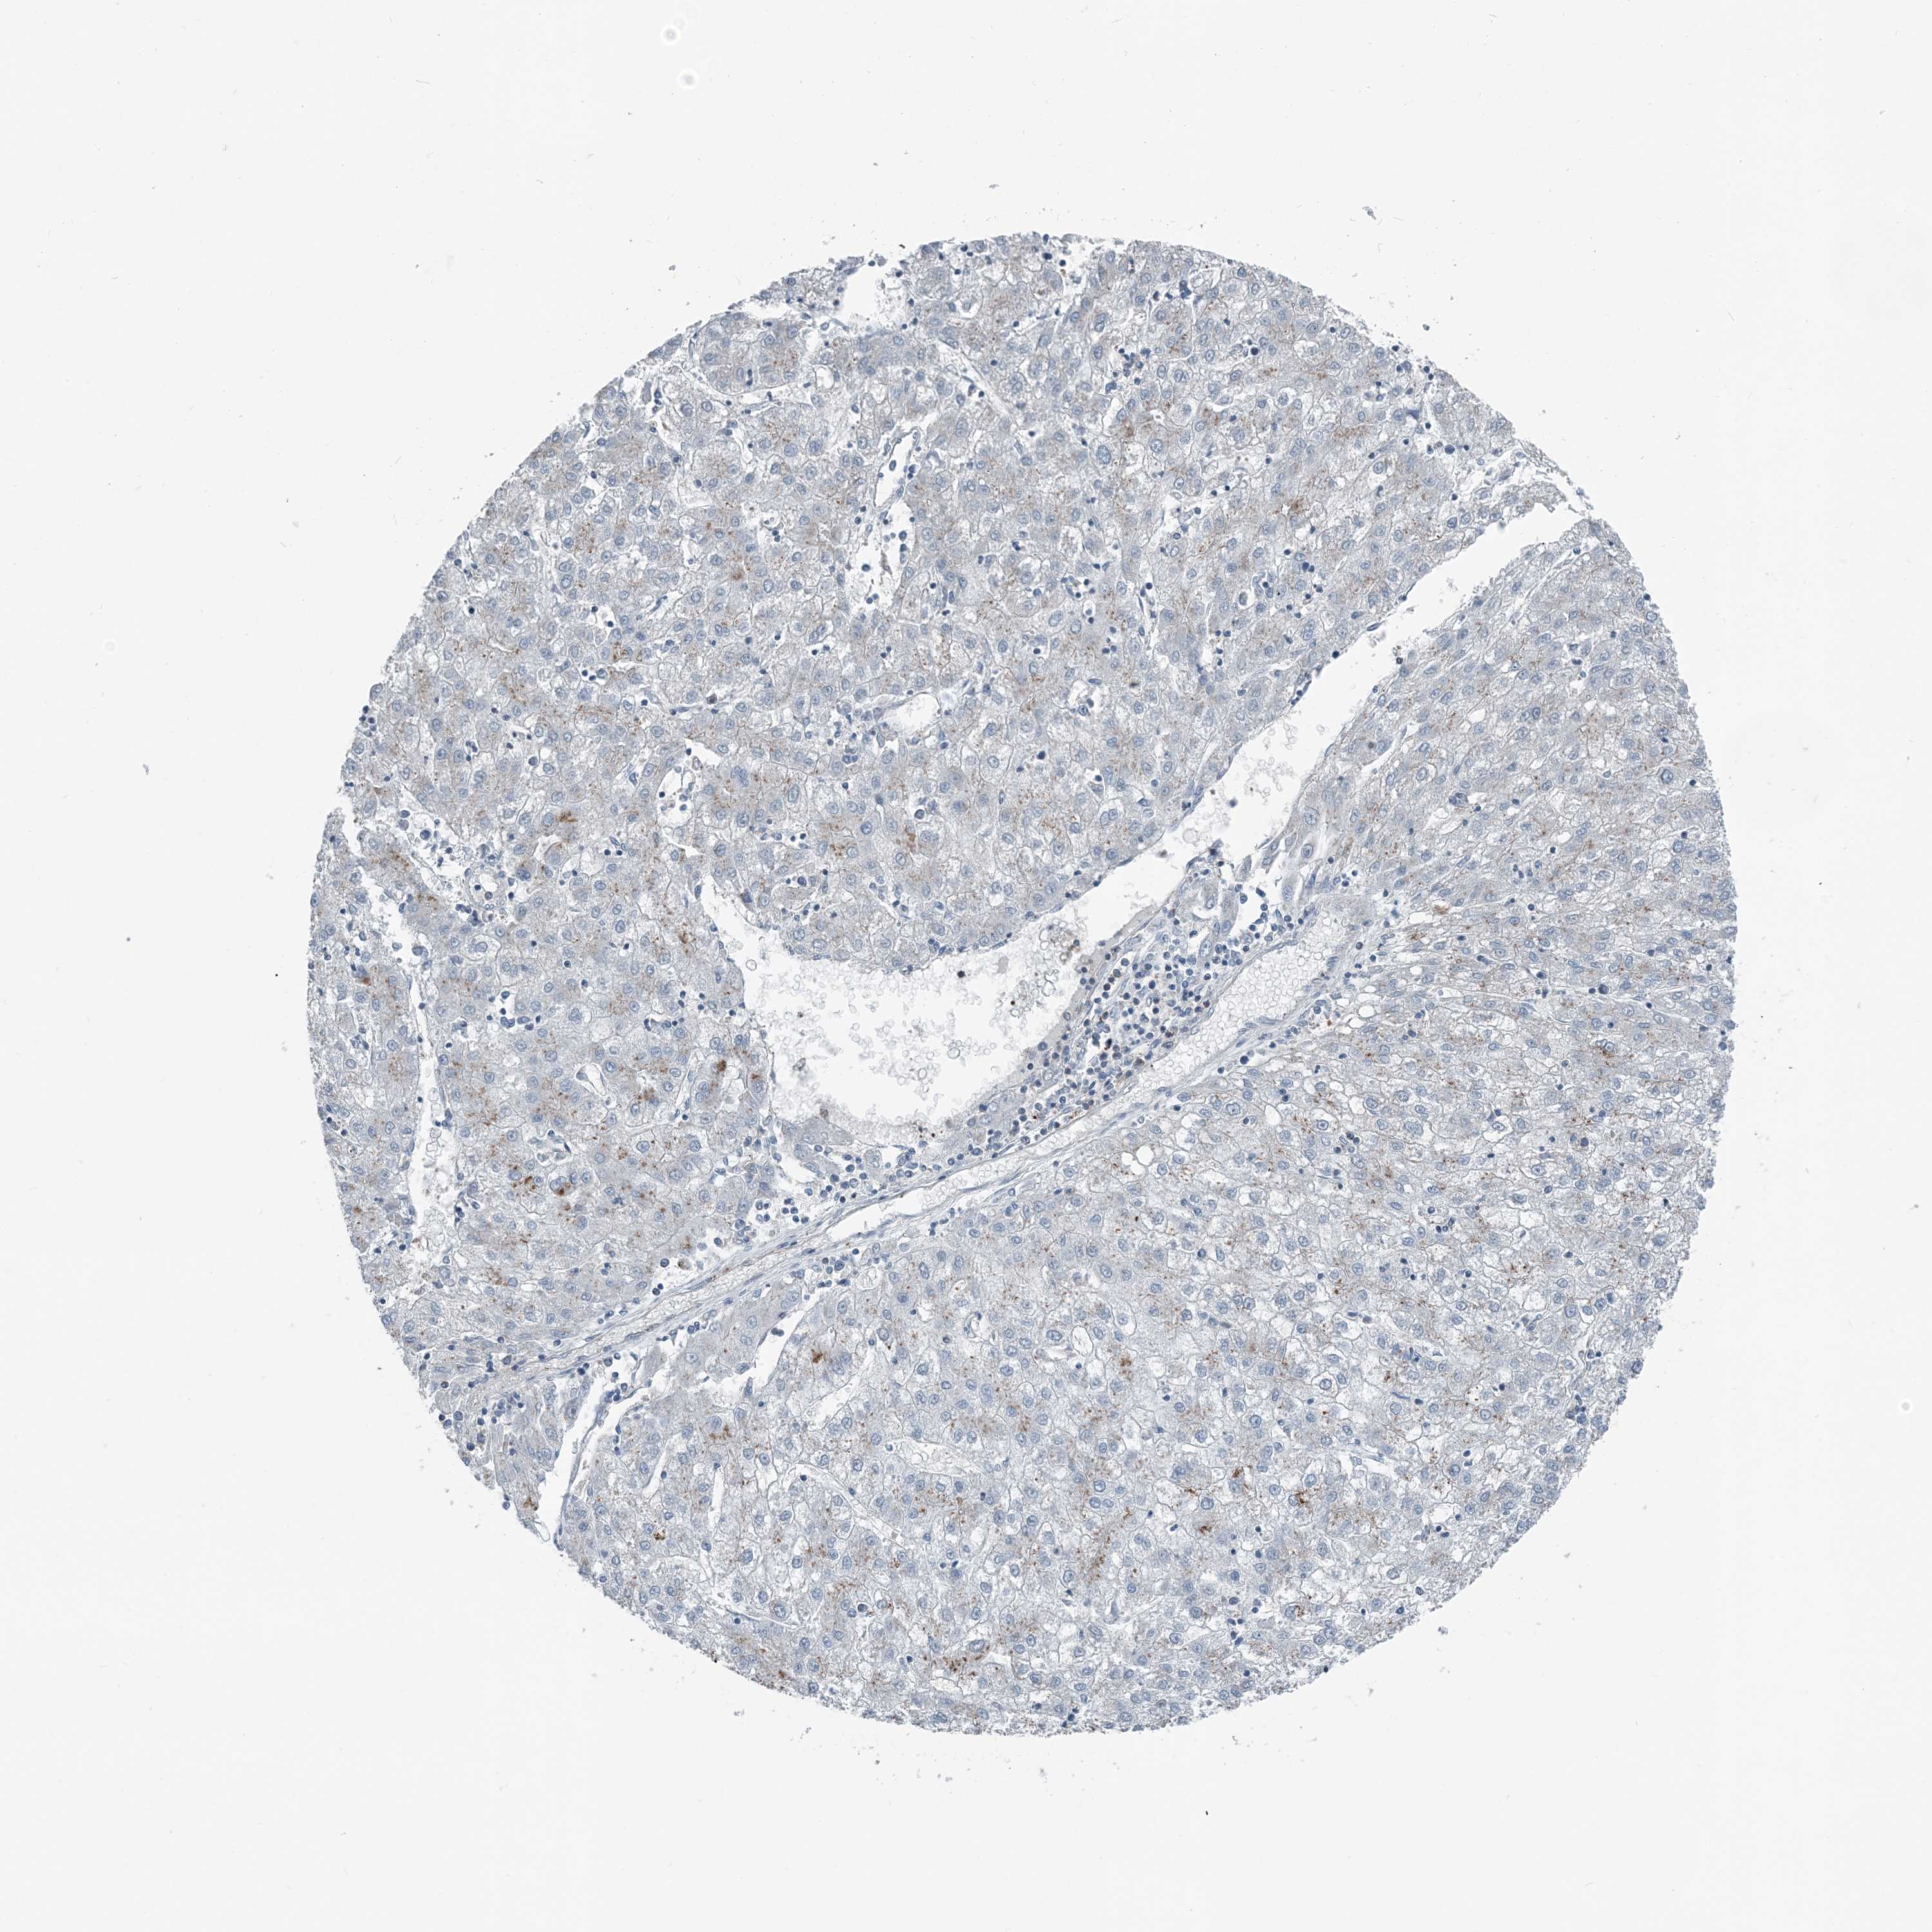

LIVER CANCER - Protein expressioni

A mouse-over function shows sample information and annotation data. Click on an image to view it in a full screen mode. Samples can be filtered based on level of antibody staining by selecting one or several of the following categories: high, medium, low and not detected. The assay and annotation is described here.

Note that samples used for immunohistochemistry by the Human Protein Atlas do not correspond to samples in the TCGA dataset.

Antibody stainingi

Antibody staining in the annotated cell types in the current human tissue is reported as not detected, low, medium, or high, based on conventional immunohistochemistry profiling in selected tissues. This score is based on the combination of the staining intensity and fraction of stained cells.

Each image is clickable and will lead to virtual microscopy that enables deeper exploration of all samples and also displays staining intensity scores, fraction scores and subcellular localization as well as patient and tissue information for each sample.

Antibody CAB037077

Cholangiocarcinoma

Carcinoma, Hepatocellular, NOS